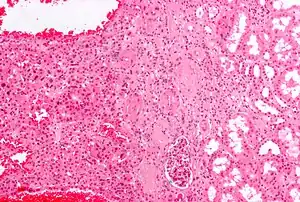

Micrograph of a renal oncocytoma. H&E stain.

Renal oncocytoma is thought to arise from the intercalated cells of collecting ducts of the kidney. It represents 5% to 15% of surgically resected renal neoplasms.

An oncocytoma is an epithelial tumor composed of oncocytes, large eosinophilic cells having small, round, benign-appearing nuclei with large nucleoli.